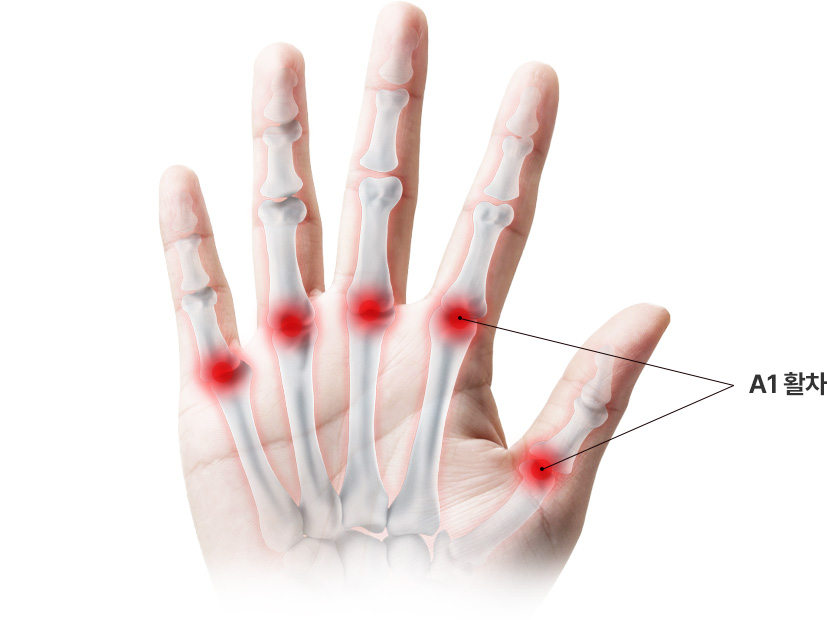

손가락의 과도한 사용과 관련 있는 병으로 손가락을 굽히는 힘줄의 병입니다.

학술적으로는 협착성 굴곡건염이라고 표현하고, A1 활차라는 터널에 굽히는 힘줄이 마찰되다가 힘줄의 내부적인

변화가 일어나 병이 생긴 상태를 의미합니다. 내부적인 변화가 심해질 경우 힘줄이 부어 결절을 이룰 수도 있는데

이러한 경우 A1 활차에 끼어서 딸깍 거리거나 걸려서 안 펴지는 증상이 생깁니다.

손가락을 굽히거나 펼 때 통증이 있고 A1 활차에

해당하는 부위를 눌렀을 때 심한 통증이 발생